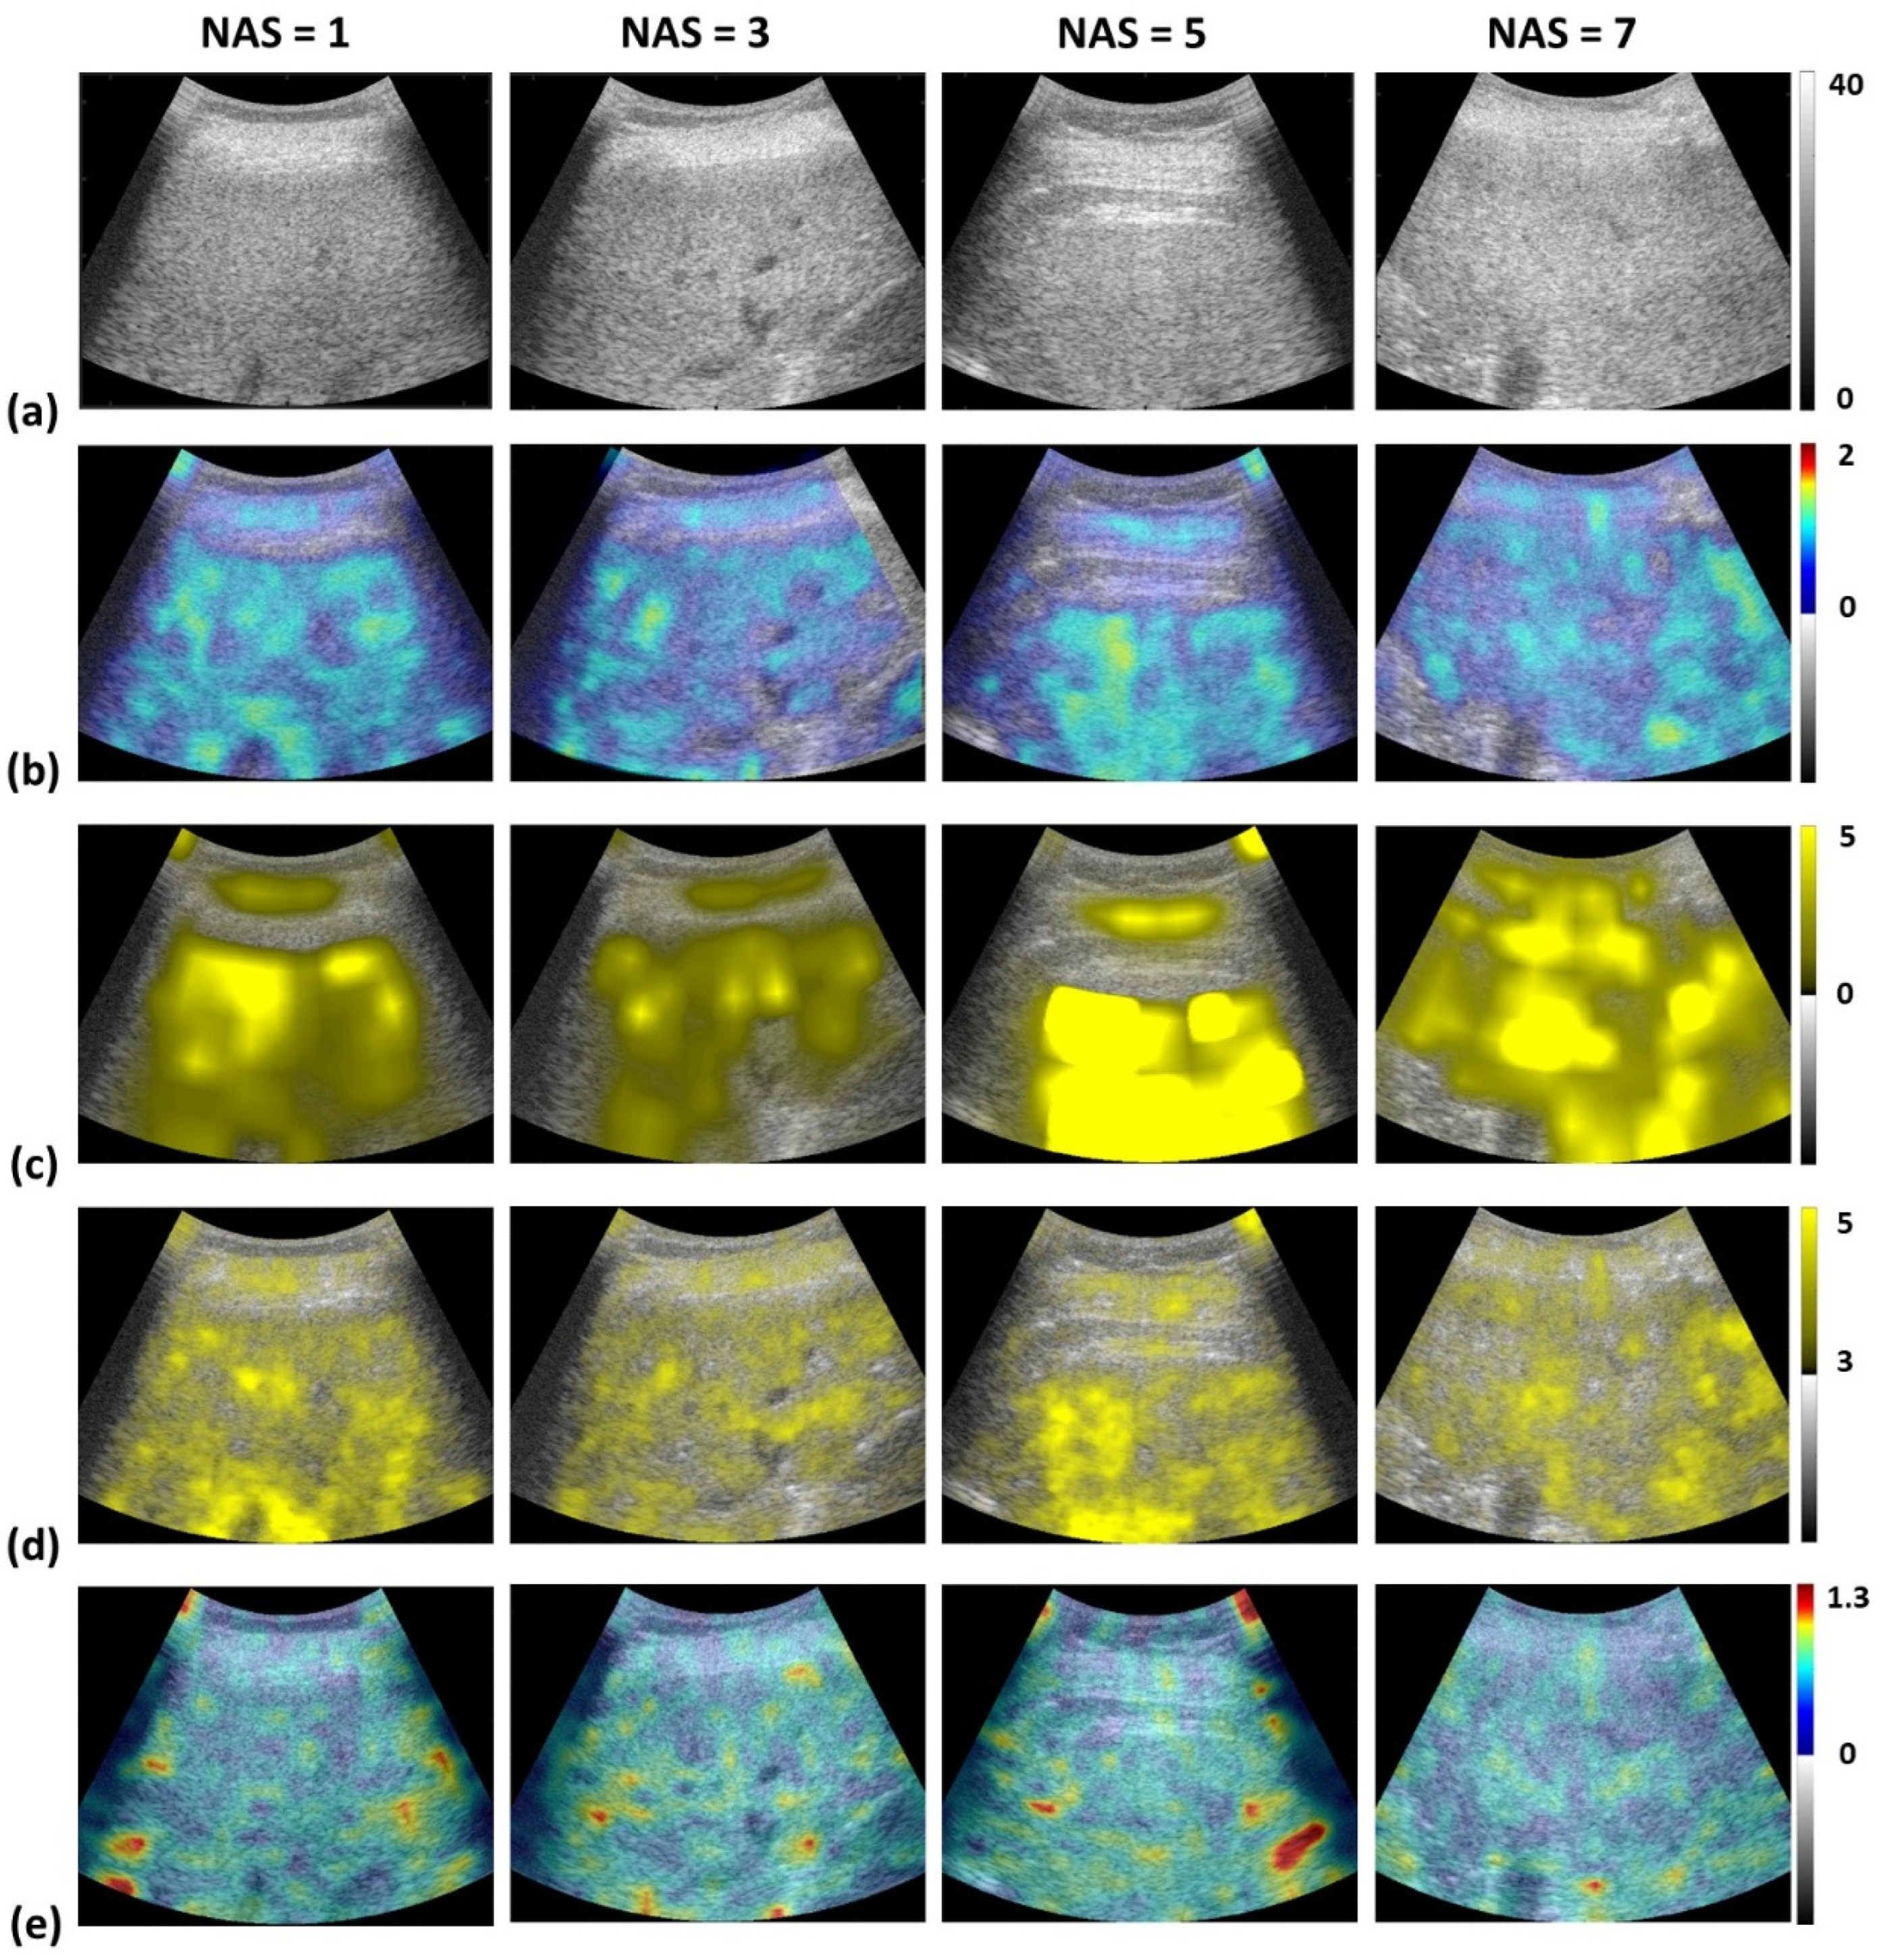

2.4. Envelope Statistics and Attenuation Imaging